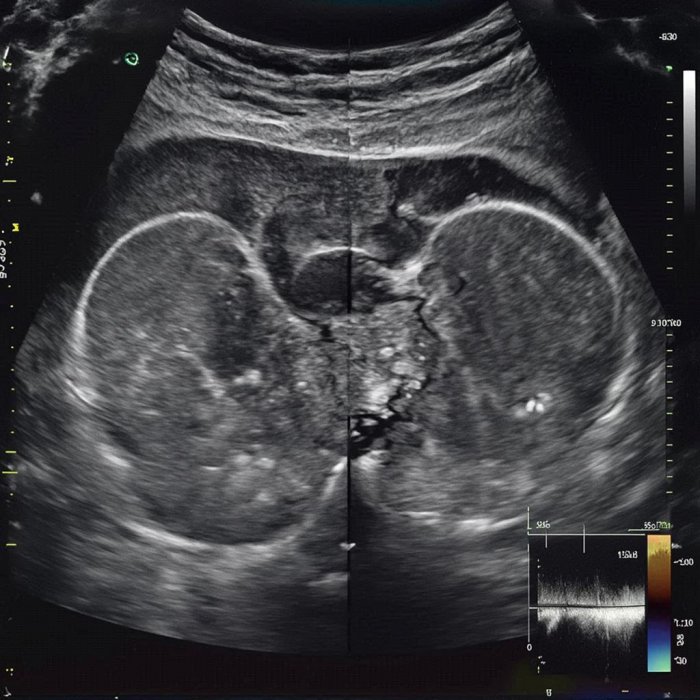

Test koji se rutinski primenjuje u proceni tiroidnog nodusa je ultrazvučni pregled.

Test koji se rutinski primenjuje u proceni tiroidnog nodusa je ultrazvučni pregled. Ovaj jednostavni postupak koristi ultrazvučne talase koji se emituju iz ručnog transdjusera (prenosnika, sonde) koji se stavlja iznad tiroidne žlezde. Da bi se izbeglo rasipanje na površini dodira koristi se gel kojim se premaže koža iznad žlezde. Test je jeftin, pouzdan, bezbolan i potpuno bezbedan. Obično ne traje duže od 5 do 10 minuta a rezultat je odmah poznat. Nije uvek potrebno da se svaki nodus ispituje ultrazvukom ali je to danas već postalo rutina.

Ima nekoliko ultrazvučnih karakteristika koje pomažu u razlikovanju sumnjivih od bezbednih tiroidnih nodusa. Mora se uvek imati na umu da ultrazvuk ne može da napravi razliku između benignog i malignog nodusa! Postupak na prvome mestu može da ukaže da neka promena ima manju verovatnoću da bude maligna ali ne može da isključi kancer.

Ultrazvučne osobine koje podržavaju verovatnoću benigne prirode nodusa:

• Oštra granica nodusa

• Nodus ispunjen tečnošću (cista)

• Više nodusa u štitastoj žlezdi

• Nema krvotoka u nodusu (nema tkiva, verovatno cista)